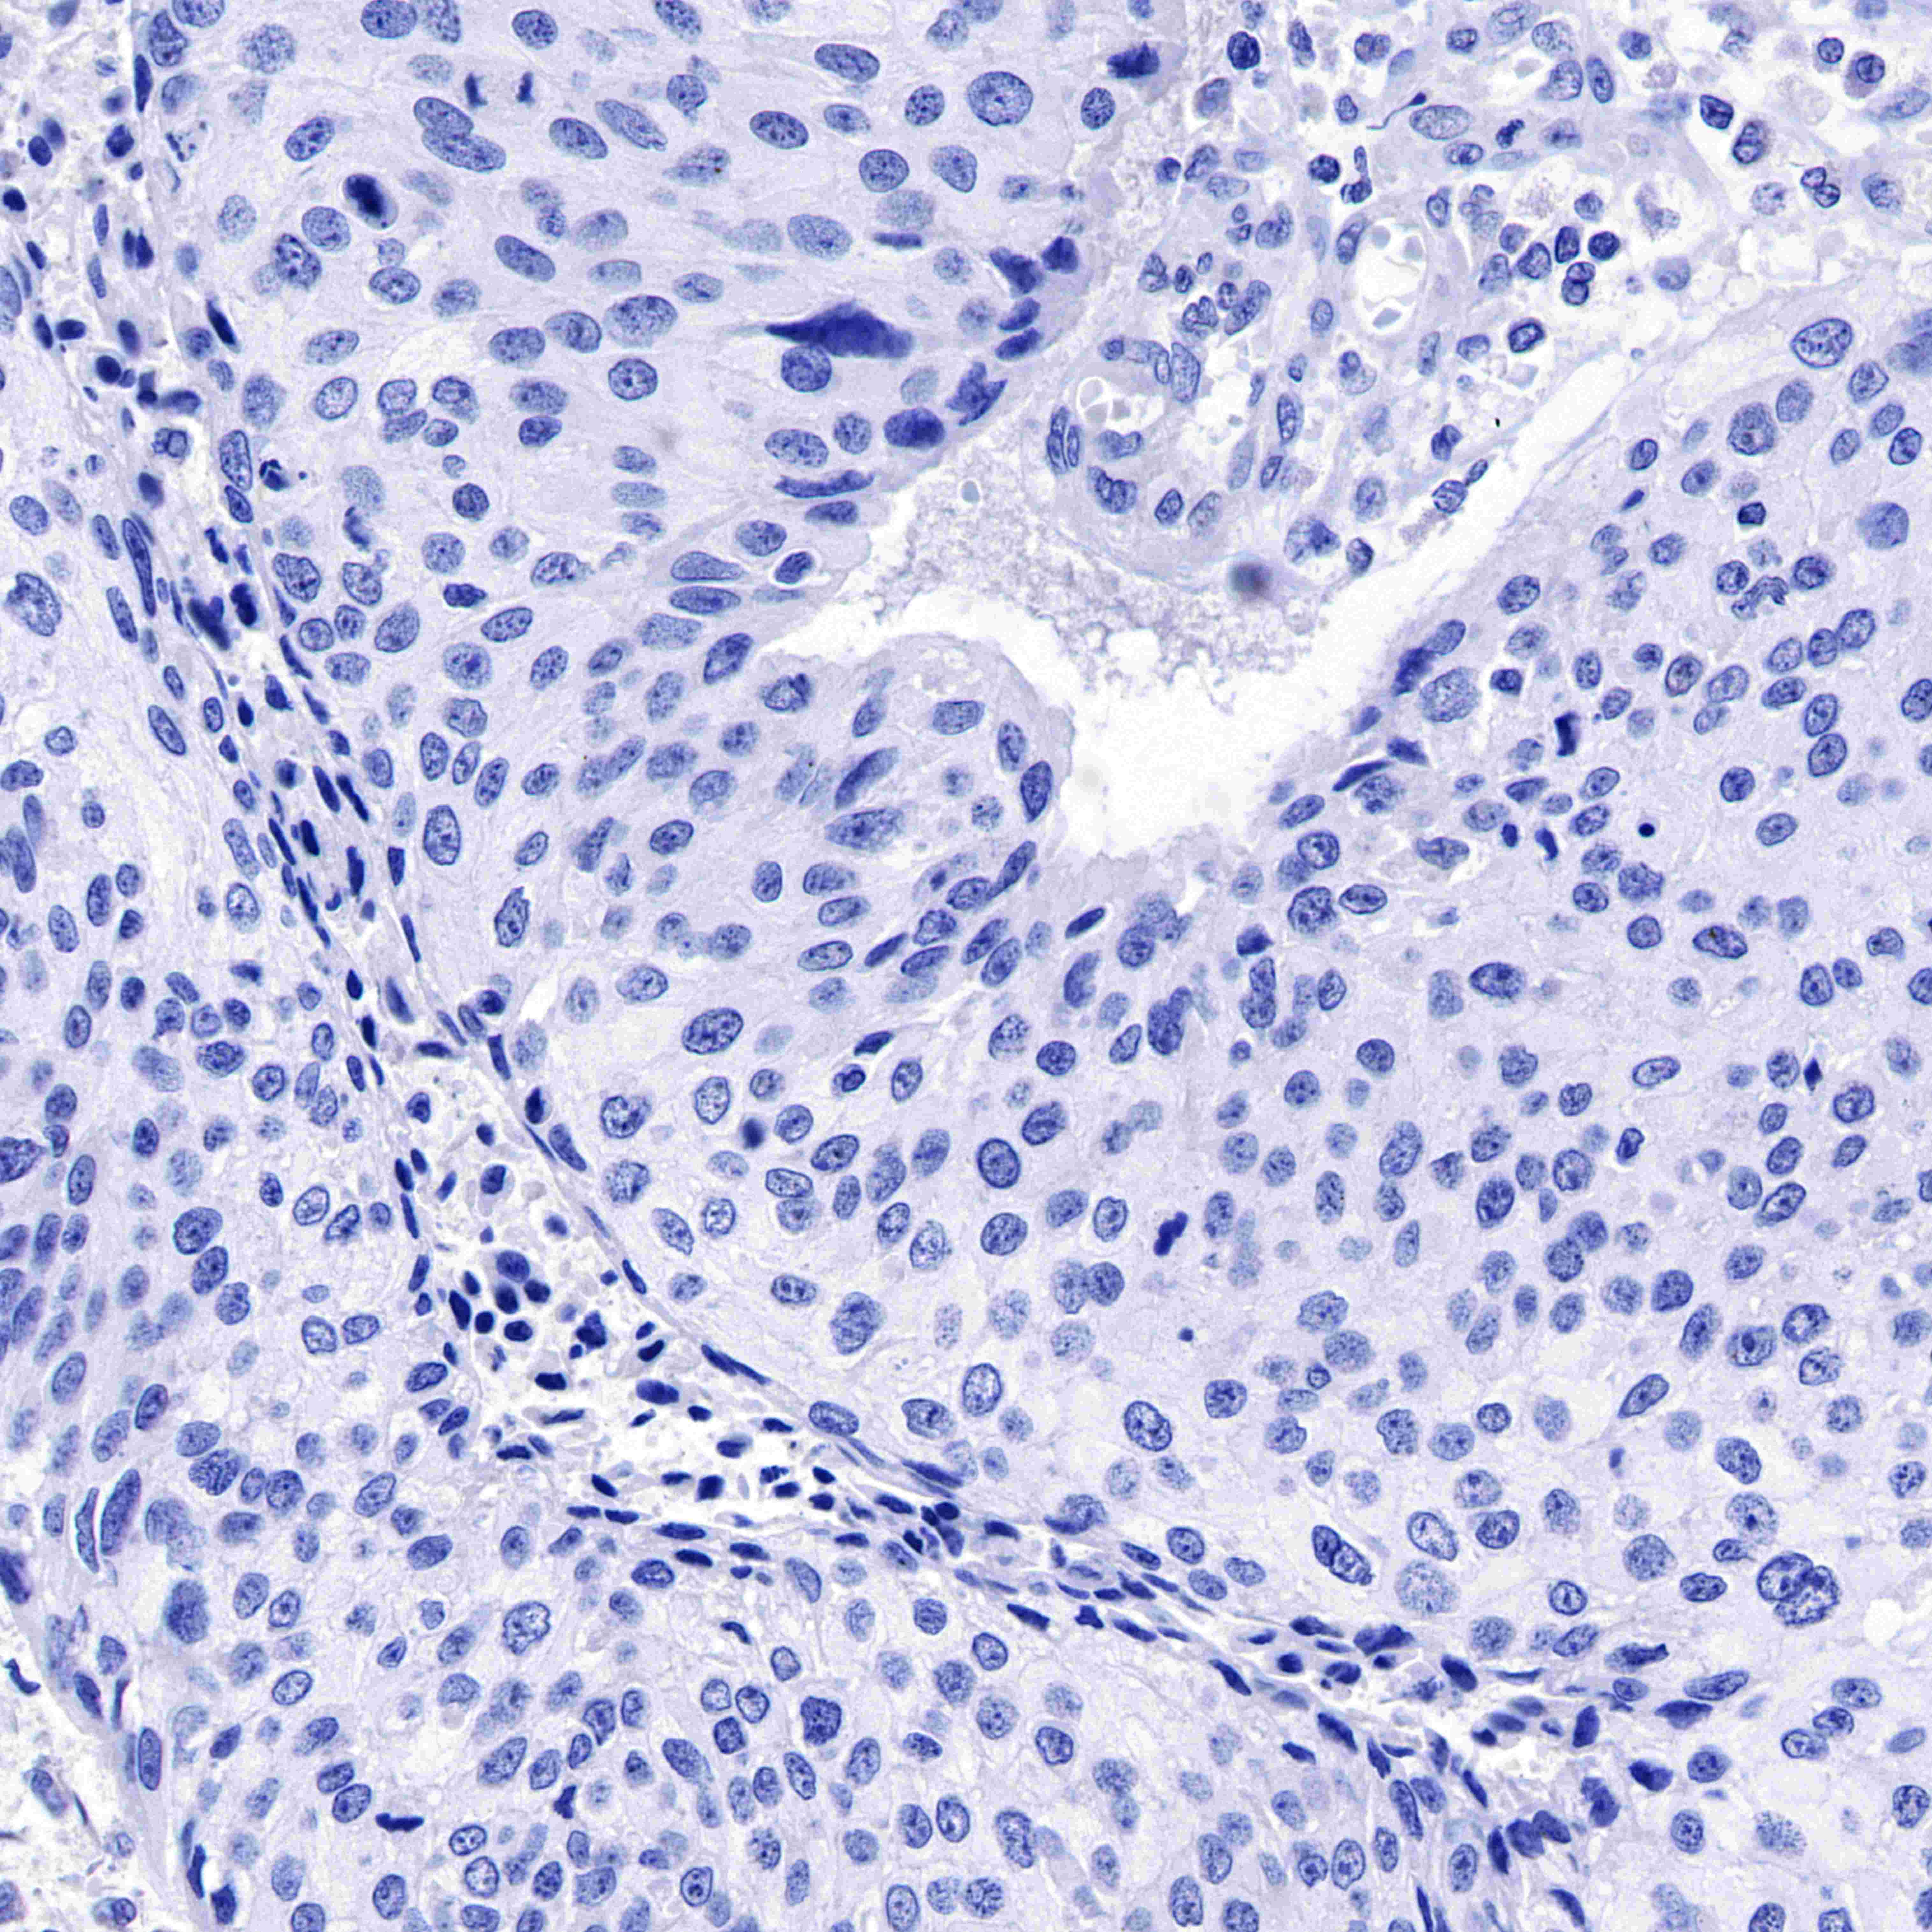

IHC-P |

1:500-1:1000 |

Background